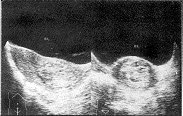

中国超声医学杂志990135 患者女,22岁,因停经50天大量阴道流血5天就诊,门诊以不全流产收住院。患者呈贫血貌,早孕反应较重。妇科检查:外阴正常,阴道通畅有积血,宫颈光滑,宫体正常大、质软、活动度可,双侧附件正常,尿HCG阳性,B超检查:子宫体前位,大小为5.5cm×3.5cm×4.4cm,浆膜、肌层回声正常,宫腔线清晰,居中,宫颈膨大、前后径4.4cm,宫颈管内探及4.3cm×3.9cm闪亮密集光点及大小不等相间小暗区,似蜂窝状(附图),宫颈内口关闭,双侧附件正常。B超诊断:子宫颈管内完全性葡萄胎。经产科钳刮后送病检,病理诊断:水泡状胎块。

附 图